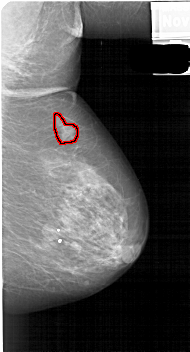

A_1889_1.LEFT_MLO

LEFT_MLO LINES 5386 PIXELS_PER_LINE 2866 BITS_PER_PIXEL 12 RESOLUTION 43.5 NON_OVERLAY

FILE: A_1889_1.RIGHT_MLO.OVERLAY

TOTAL_ABNORMALITIES 1

ABNORMALITY 1

LESION_TYPE MASS SHAPE IRREGULAR MARGINS ILL_DEFINED

ASSESSMENT 4

SUBTLETY 4

PATHOLOGY BENIGN

TOTAL_OUTLINES 1

BOUNDARY